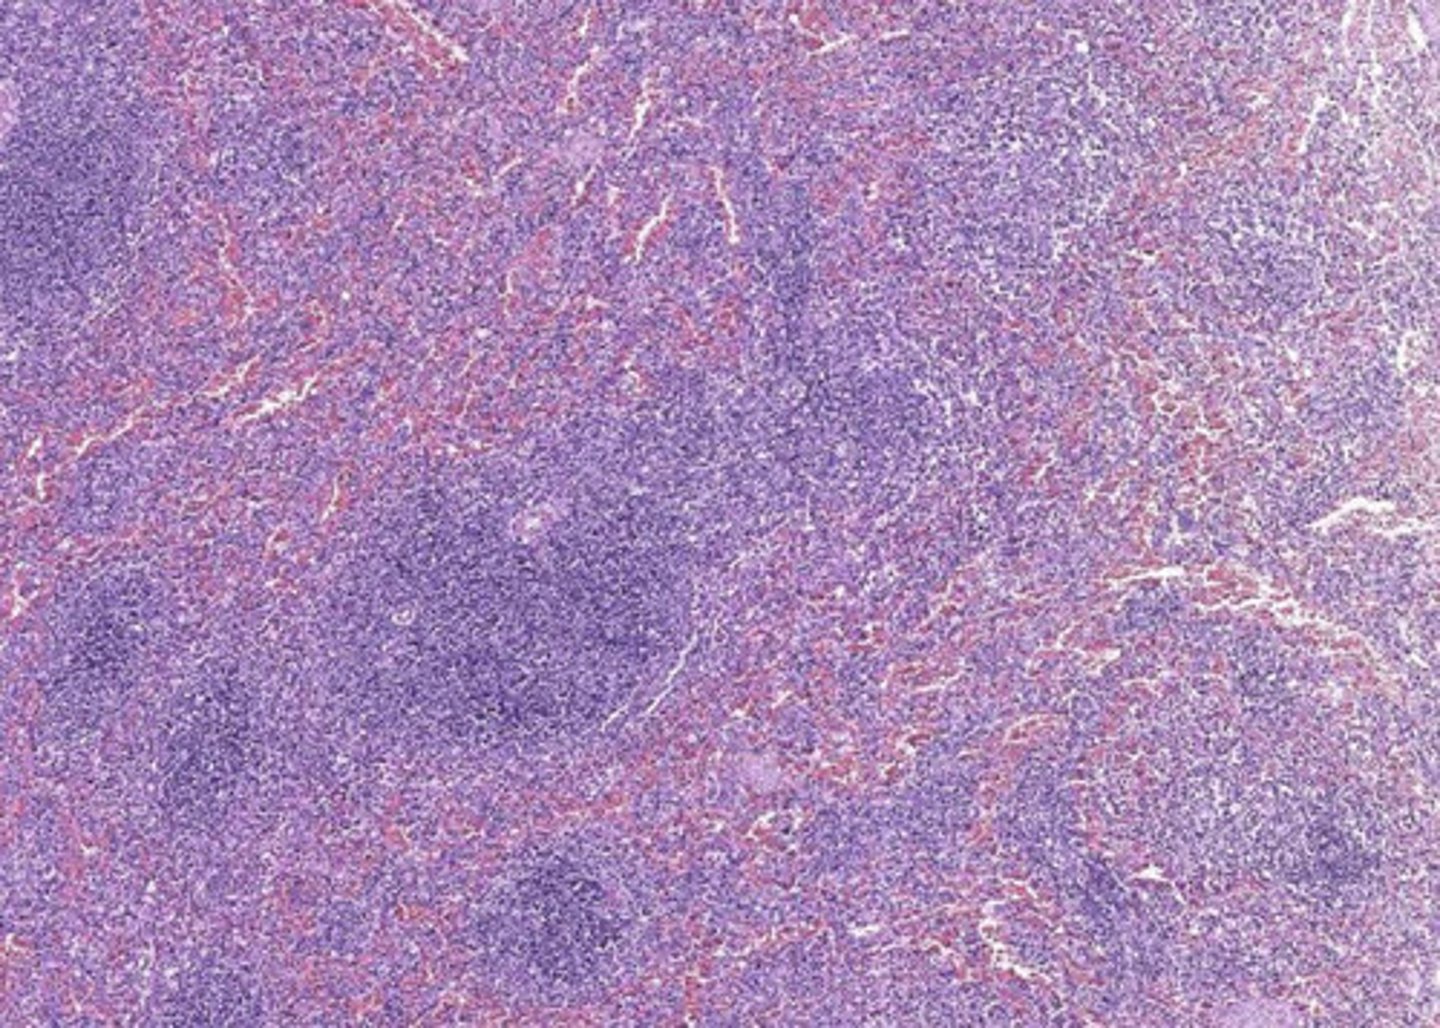

lymph node

what is this?

lymph node

what is this?